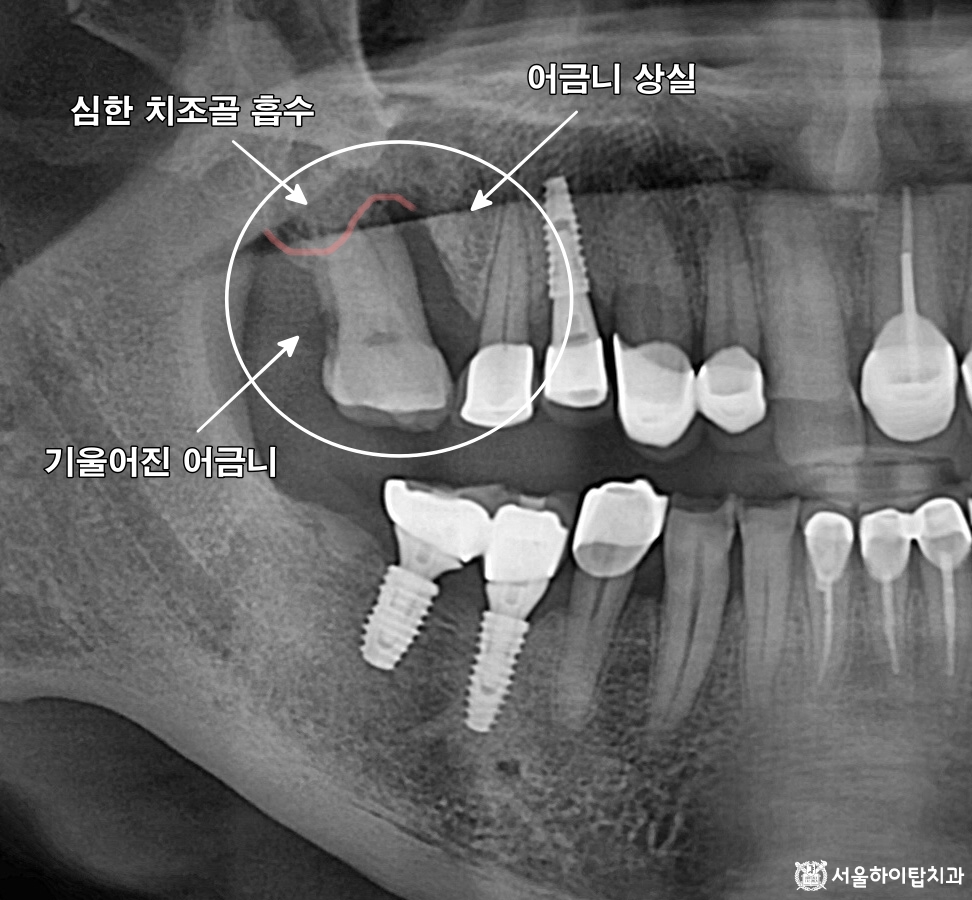

십정동 치과 상실된 치아가 불러오는 연쇄적 문제? 치조골 흡수와 기울어진 어금니, 뼈이식 동반 임플란트 과정 동암역 치과 : 균형 잡힌 저작이 중요한 이유, 전반적으로 손상된 치아 및 잇몸 임플란트를 통해 저작 기능 개선 간석역 치과 치주염으로 인한 치조골 흡수, 치아 파절 및 마모까지 임플란트 가상 시뮬레이션을 통한 안전한 수술 과정 1 2 Next Archives 2026년 4월 2026년 3월 2026년 2월 2026년 1월 2025년 12월 2025년 11월 Categories 미분류 신경치료 심미 치료 임플란트